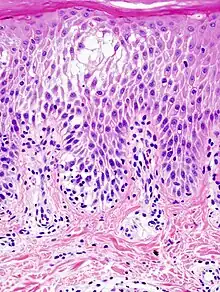

Histopathological image of dyshidrotic dermatitis, showing focal spongiotic change in the epidermis.

Spongiosis is mainly intercellular[1] edema (abnormal accumulation of fluid) in the epidermis,[2] and is characteristic of eczematous dermatitis, manifested clinically by intraepidermal vesicles (fluid-containing spaces), "juicy" papules, and/or lichenification.[3] It is a severe case of eczema that affects the epidermis, dermis or subcutaneous skin tissues.[4] The three types of spongiotic dermatitis are acute, subacute and chronic.[4] A dermatologist can diagnose acute spongiotic dermatitis by examining the skin during an office visit, but a biopsy is needed for an accurate diagnosis of the type.